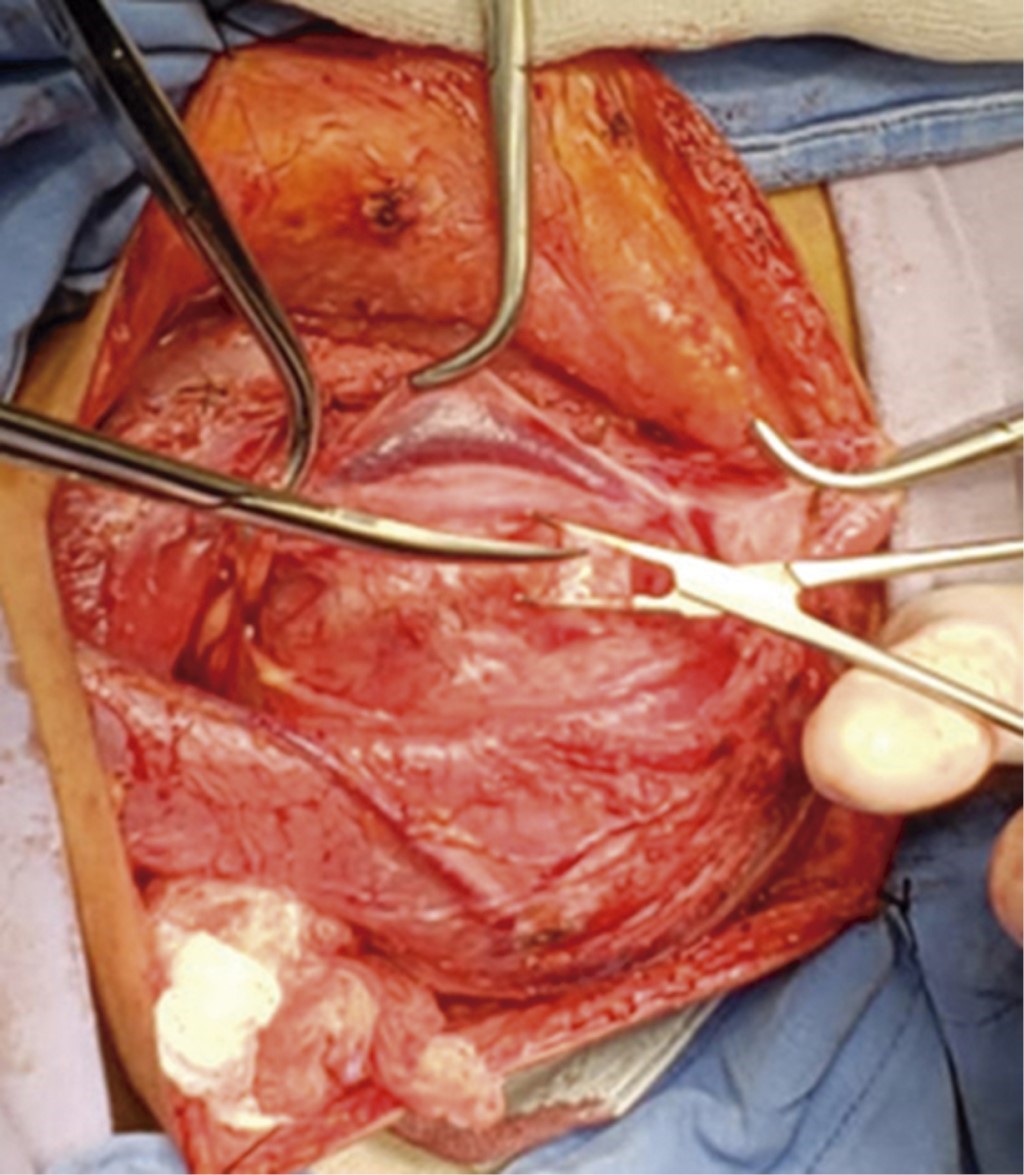

The study protocol was followed, and the surgical procedure was programmed. On the operating table with the patient in supine decubitus with Rossier position, a cervicotomy was performed through a Paul André cervical incision. After dissecting by planes (skin, subcutaneous cellular tissue, platysma), the sternocleidomastoid muscle was located, and a tumor located in the parapharyngeal space between the internal jugular vein and carotid artery (Figure 5) was found; it was dissected and enucleated, and a meticulous subcapsular dissection was performed trying to preserve the functions of the nerve of apparent origin, in this case, the X cranial nerve, to avoid its resection. The piece was sent to pathology; hemostasis was performed, and a negative pressure closed drainage of type Drenovac of 1/8 was placed. The surgical incision was closed by planes; in the fascia, Vicryl 2-0 was used, and the skin was approached with a nylon 3-0 intradermal stitch, and the surgical event ended.